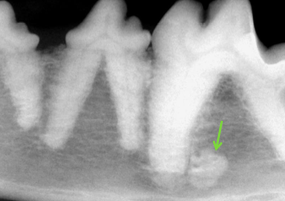

Quel est l’index parodontal de la dent 409?

A

PD4

Théorie :

- PD0 = parodonte sain, pas de perte osseuse

- PD1 = gingivite, pas de perte osseuse

- PD2 = parodontite < 25% perte osseuse

- PD3 = parodontite 25-50% ou furcation 2

- PD4 = parodontite > 50% ou furcation 3